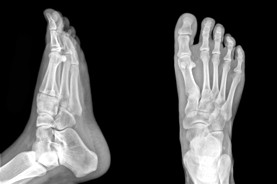

PAINFUL OR UNSIGHTLY BUNIONS?

At the Edmonton Foot Institute, our Doctors are trained to specifically treat problems associated with your feet or ankles. Below are several of the most common problems that we see on a day to day basis: